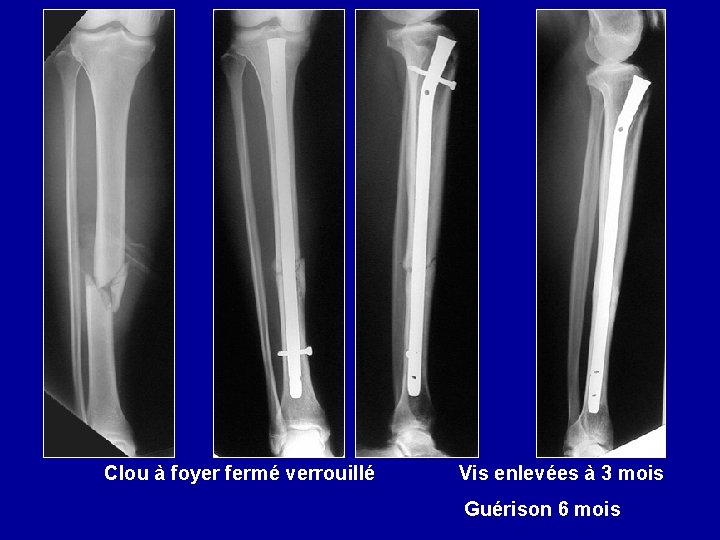

Enclouage du tibia à foyer fermé Clou simple Clou à ailettes Clou verrouillé par vis

Clou à foyer fermé verrouillé Vis enlevées à 3 mois Guérison 6 mois